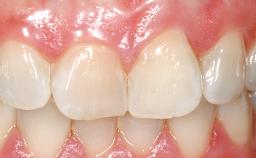

A 30-year-old female patient had lost tooth 21 and was referred to our clinic for consultation and treatment. Due to advanced apical infection, tooth 21 had been extracted two months earlier at another clinic and an acrylic-resin tooth had been bonded to the adjacent teeth. The patient desired implant treatment to avoid any damage to the adjacent natural teeth. While the patient had no history of any systemic disorder, she was a heavy smoker and exhibited medium to advanced periodontitis in the entire jaw. After the initial treatment to achieve a pocket probing depth of less than 4 mm and no bleeding on probing, a decrease in the height of the papillae mesial and distal to the extraction site and overall gingival recession were observed.

Prosthesis Type FDP

Soft Tissue Contour and Volume Slightly compromised